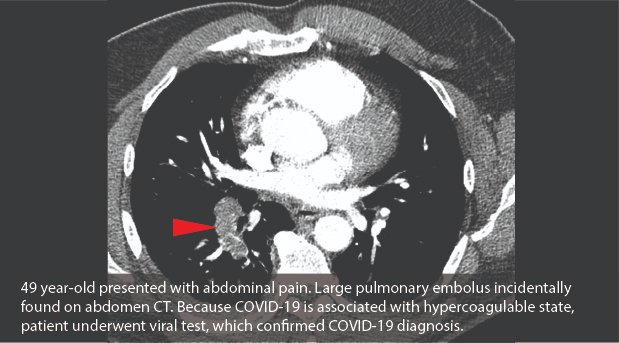

Patients with #COVID19 are often coagulopathic, as described in @NEJM case report bit.ly/3dnsw91. See @DivRadiology case of incidentally found pulmonary embolus on abdomen CT which led to diagnosis of #COVID19.

While #CT is not used as a first-line diagnostic test for #COVID19, #radiologists are finding "incidental" COVID pneumonia in asymptomatic patients.